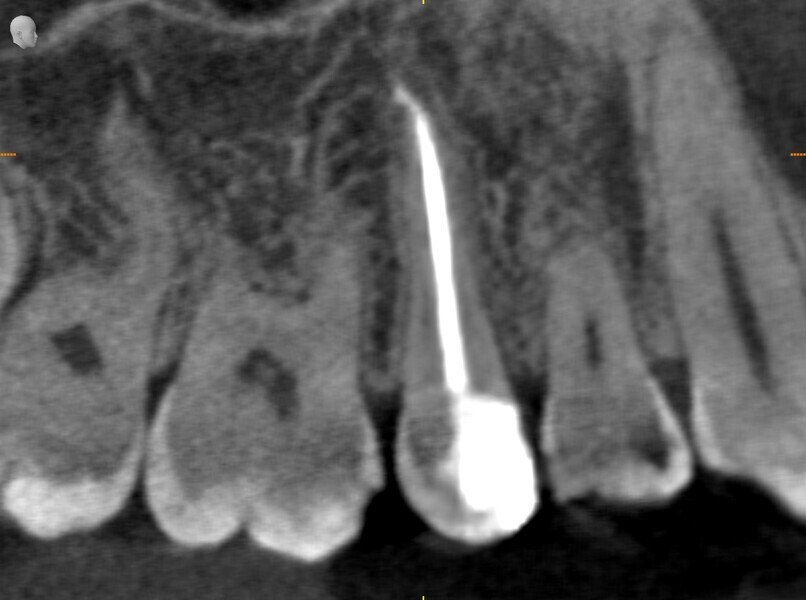

Instrumentation was then performed with the R25 RECIPROC blue up to the level of the split, and the split was prepared with the 12.5/0.04 R-PILOT (VDW; Fig. 18). The final irrigation protocol was performed with copious amount of fluids (sodium hypochlorite and citric acid with a final rinse of distilled water; Fig. 19). Obturation was performed with the piston technique, and the restoration was done with composite material (Fig. 20). The patient was referred to the prosthodontist for final restoration. On the final CBCT scan, it was clearly visible that the piston technique had helped to obturate the deep split in the apical area (Fig. 21).